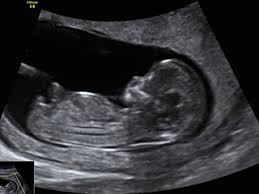

Résultat de recherche d'images pour "age gestationnel echographie" Les mesures biométriques échographiques permettent de déterminer l’âge gestationnel en fonction de l’hypothèse selon laquelle la taille de l’embryon ou du fœtus correspond à l’âge de ce dernier. Les variations biologiques de la taille étant moins importantes au cours du premier trimestre qu’au cours du troisième trimestre, l’estimation échographique de l’âge gestationnel est donc plus précise au cours du premier trimestre que plus tard dans le cadre de la grossesse

Lorsqu’une échographie menée au deuxième ou au troisième trimestre est utilisée pour déterminer l’âge gestationnel, une combinaison de multiples paramètres biométriques (diamètre bipariétal, périmètre tête, périmètre abdominal et longueur du fémur) devrait être utilisée, plutôt que de n’avoir recours qu’à un seul paramètre.